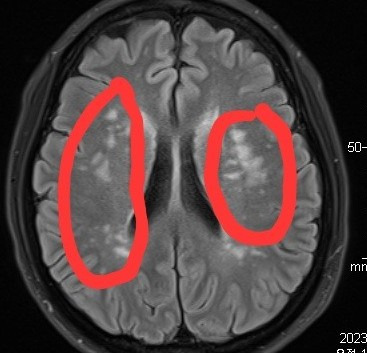

뇌에 흰부분은 병변인가요? 엠알아이 결과 궁금해요

저부분이 하야면 안되는곳인가오,,?

해당부위가 고신호로 보이는 것은 카다실 뿐만 아니라 멜라스나 기타 다른 질환때도 관찰 가능하며 병적인 상태가 아닌 백질의 뇌소혈관질환에서도 보일수 있습니다.

MRI에서 뇌실질은 어둡게 보여야 합니다

주변보다 밝은 경우 해당부위에 허혈 혹은 경색이 있다고 판단을 합니다

첨부해주신 영상은 머리 MRI 중 FLAIR라는 영상입니다.

흰 부분은 뇌의 백질에 병변이 발생한 것으로, 만성적인 허혈증에 의해 발생한 병변일 가능성이 높고 CADASIL과 연관되었을 가능성이 있습니다.